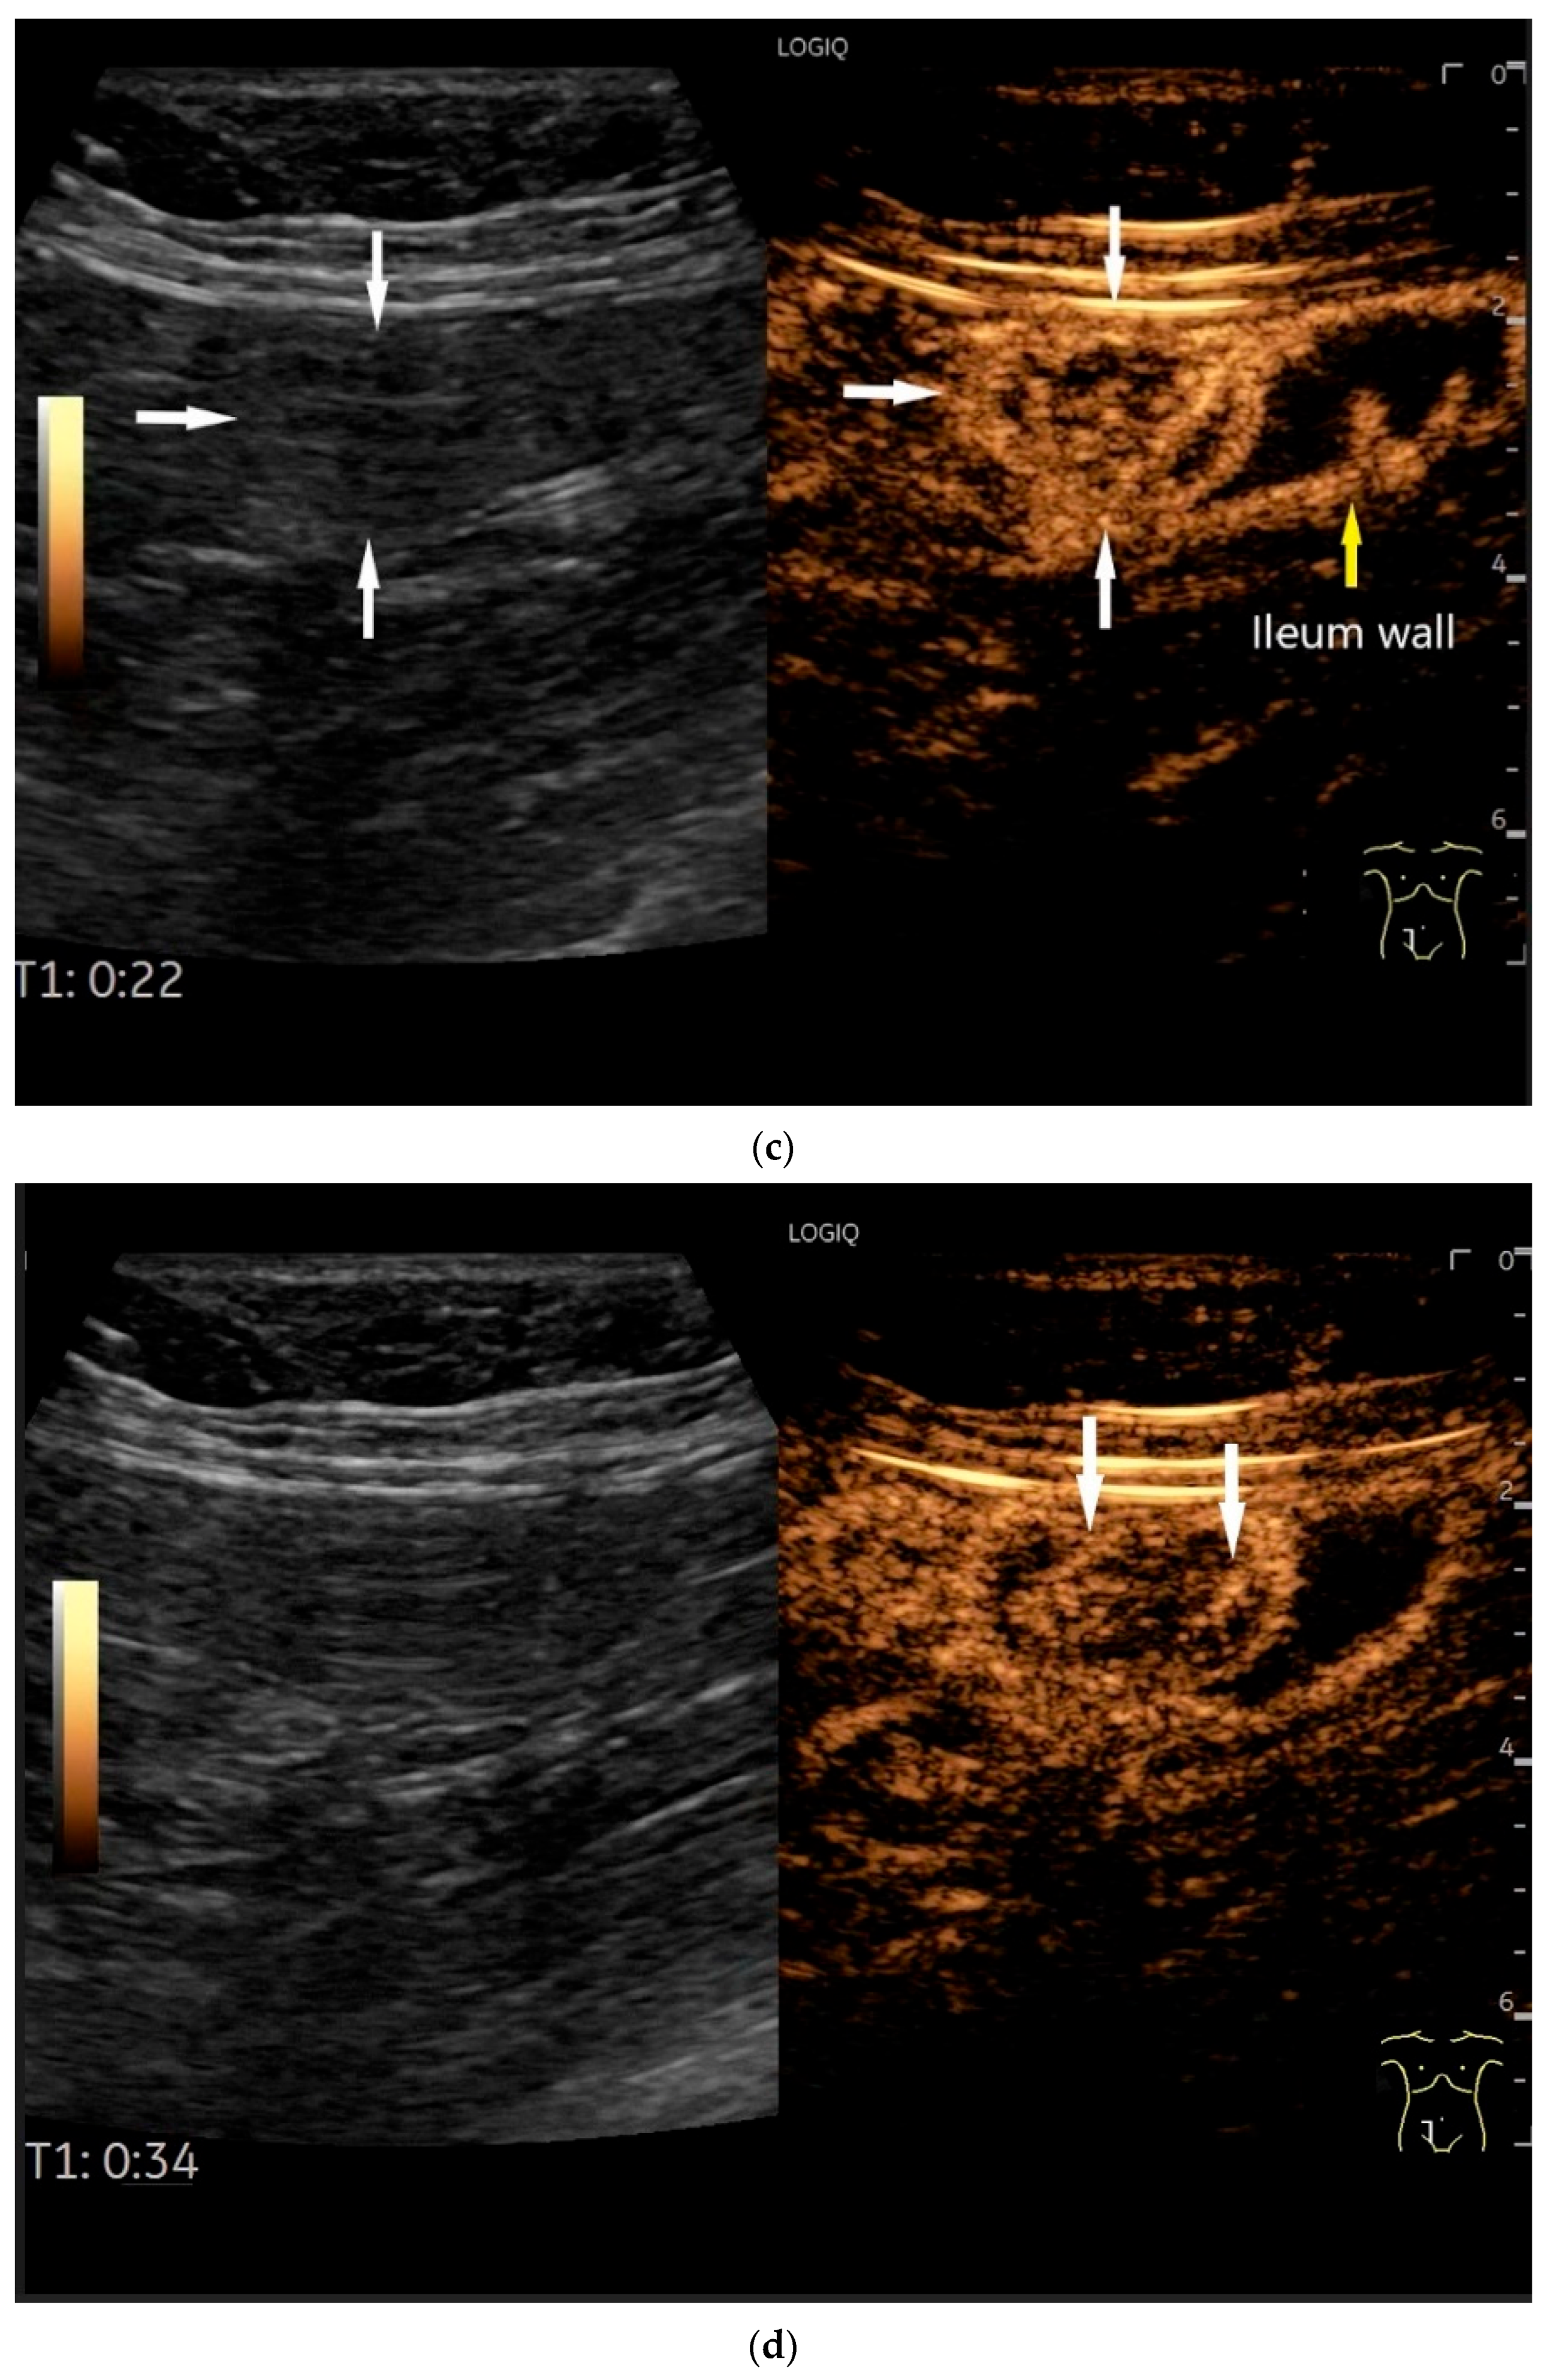

- Zhao, J.Y.; Zhuang, H.; Luo, Y.; Su, M.G.; Xiong, M.L.; Wu, Y.T. Double contrast-enhanced ultrasonography of a small intestinal neuroendocrine tumor: A case report of a recommendable imaging modality. Precis. Clin. Med. 2020, 3, 147–152. [Google Scholar] [CrossRef]

| Neuroendocrine tumor | Small, nodular hypoechoic wall thickenings, mostly in the submucosa with spreading into the other layers. Usually with small vessels on CDI. Regionally enlarged lymph nodes. Multilocular manifestations are possible. |